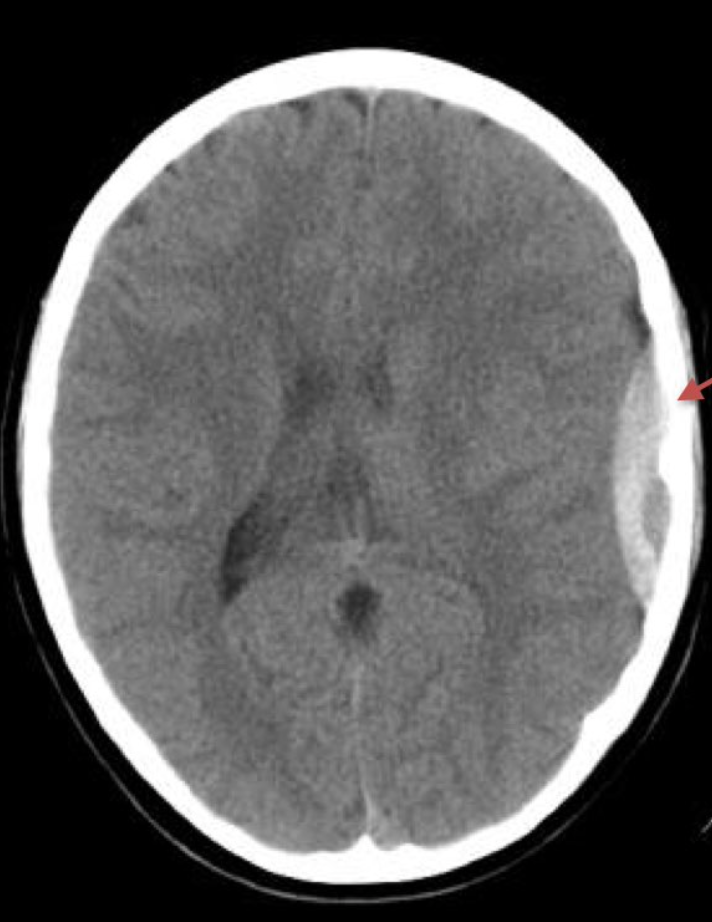

epidural haematoma

subarachnoid haemorrhage

subdural haematoma

infarct